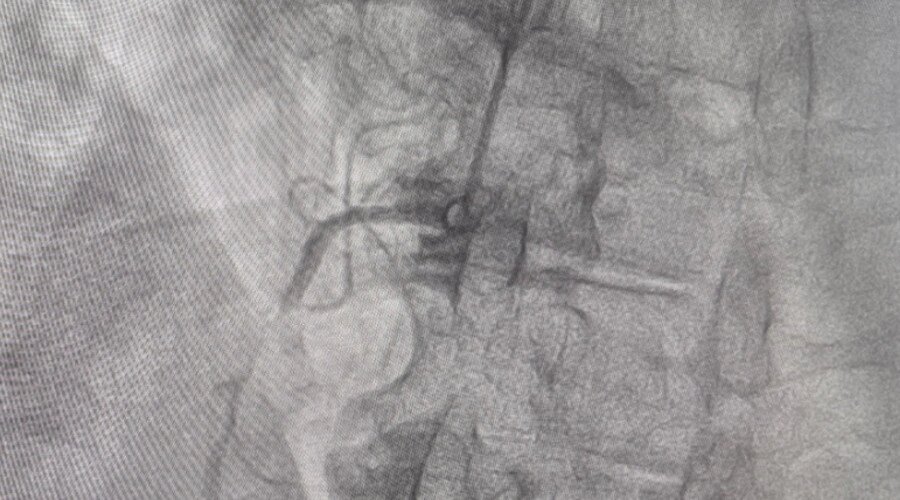

Как сообщает Балаковская городская клиническая больница (БГКБ), в приемную учреждения был доставлен 88-летний житель Пугачевского района с острыми болями в груди. После выполнения ангиографии выяснилось, что в работе двух из трёх коронарных сосудов существуют серьезные проблемы, причем один из сосудов был практически полностью без кровотока. Врачи провели консилиум, на котором было принято решение восстановить проходимость инфарктосвязанной артерии. При проведении коронарографии выяснилось, что пораженный сосуд гораздо больших размеров, чем фиксировалось ранее.

- Это говорит о том, что значительная часть сердца на момент инфаркта миокарда находилась без кровоснабжения и не получала кислород, - пояснил врач-рентгенэндоваскулярный хирург Павел Алимов.

Пациенту был имплантирован стент. Несмотря на возраст, мужчина перенес вмешательство удовлетворительно. Болевой синдром был купирован сразу же, при нахождении пациента на операционном столе. Из двух пораженных сосудов врачи простентировали самый проблемный. После стентирования больного перевели в отделение реанимации и интенсивной терапии для динамического наблюдения.